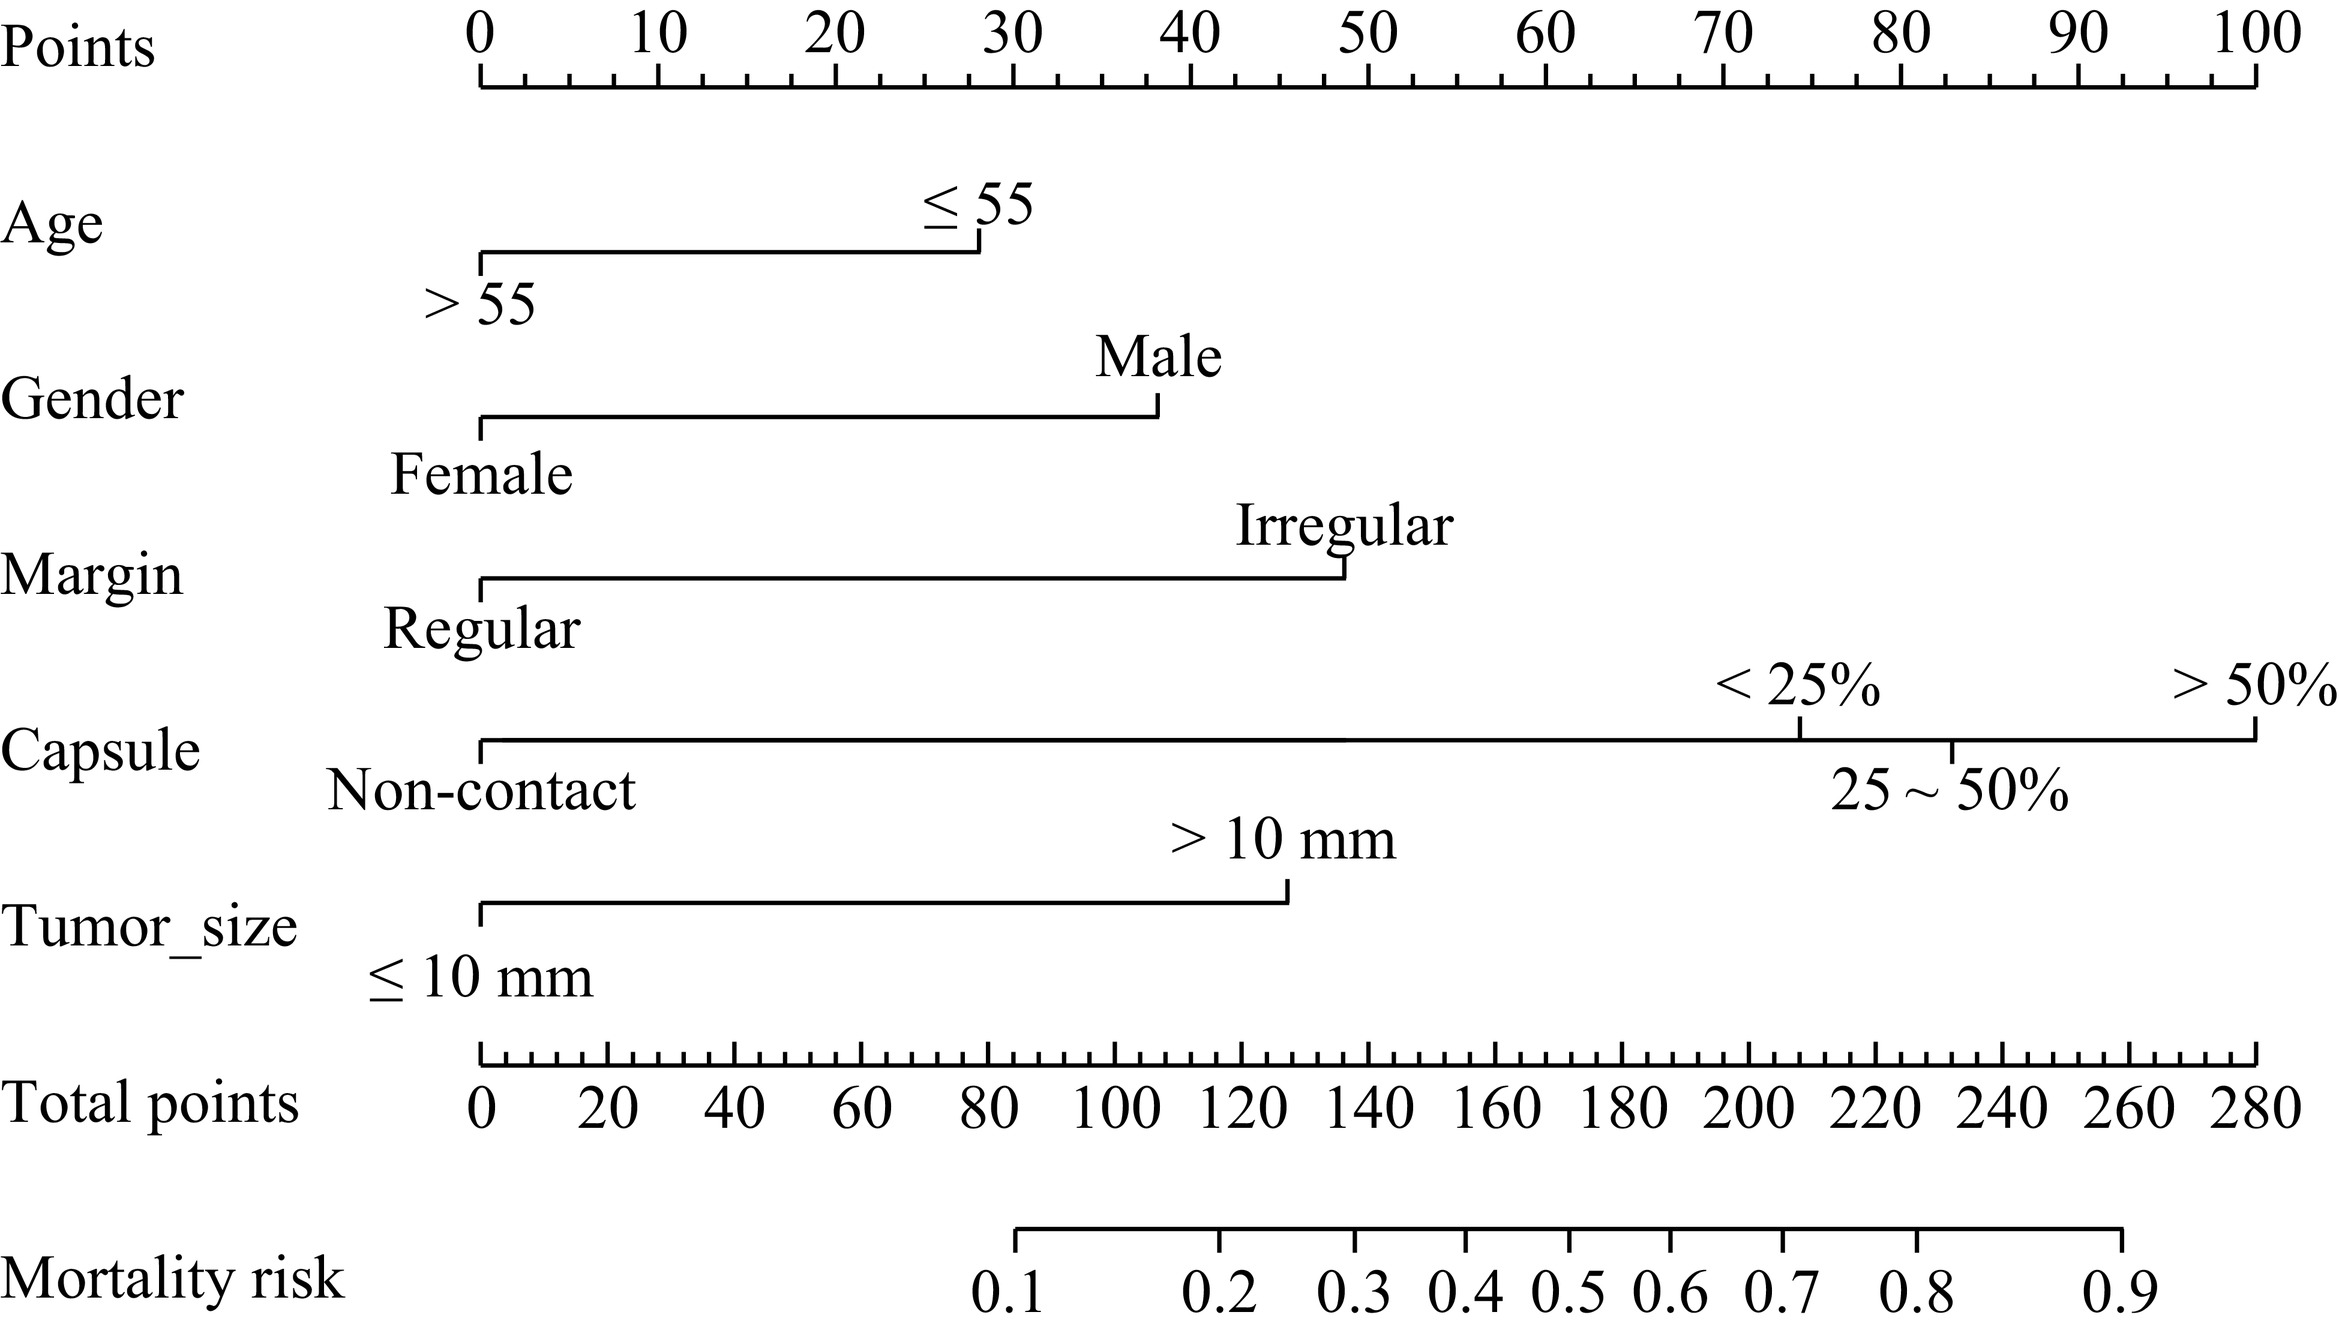

表 3 340例PTC患者CLNM的多因素logistics回归分析Table 3. Multivariate logistic regression analysis for CLNM in 340 patients with PTC变量 估计值 标准误 统计检验 Z P 截距 −2.596 0.688 −3.773 0.000 年龄(> 55) −0.755 0.332 −2.272 0.023 性别(女) −0.993 0.362 −2.739 0.006 边缘(不规则) 1.153 0.390 2.856 0.003 最大径(>10 mm) 1.051 0.362 2.898 0.003 构成(囊实性) 0.343 0.397 0.863 0.388 被膜接触 < 25% 1.791 0.622 2.879 0.004 25%~50% 2.005 0.623 3.217 0.001 > 50% 2.520 0.632 3.984 0.000 钙化 ≤3 mm 0.003 0.350 0.008 0.993 > 3 mm 0.515 0.591 0.871 0.384 340名PTC患者以7∶3随机分成训练组(n=273)和验证组(n=103),IRFs在随机分组中的差异无统计学意义(表4)。依据IRFs在多因素Logistic回归分析中的权重,在训练组构建列线图(Nomogram)(图1),并在验证组验证。结果显示,Nomogram的受试者操作特征曲线(receiver operating characteristic curve,ROC)在训练组的曲线下面积(area under the curve,AUC)为0.815(95% CI:0.761~0.870),在验证组中的AUC值0.747(95% CI:0.646~0.848)(图2)。Nomogram预测个体患者CLNM发生概率的实例演示如图3。

表 4 340例PTC患者7∶3比例随机分组中IRF的比较Table 4. Comparison of IRFs in the training and validation cohorts where 340 PTC patients were randomly divided into at a 7∶3 ratio特征 组别 统计检验 训练组(n=237) 验证组(n=103) T P 年龄分组/例(%) ≤55 141(59.5) 62(60.2) 0.015 0.904 >55 96(40.5) 41(39.8) 性别/例(%) 男 63(26.6) 25(24.3) 0.200 0.655 女 174(73.4) 78(75.7) 边缘/例(%) 规则 68(28.7) 36(35,0) 1.325 0.250 不规则 169(71.3) 67(65.0) 被膜接触/例(%) 0 45(19.0) 14(13.6) 1.903 0.593 < 25% 68(28.7) 28(27.2) 25%~50% 64(27.0) 32(31.1) > 50% 60(25.3) 29(28.2) 最大径/例(%) ≤10 mm 164(69.2) 69(67.0) 0.162 0.687 >10 mm 73(30.8) 34(33.0) ![]() 图 3 Nomogram预测CLNM的性能演示(界值为0.303)注:患者1,男性,44岁,PTC病例,CLNM阳性。CT平扫示右叶中下部类圆形病灶,内见钙化,与甲状腺被膜接触约75%(a),增强后不均匀强化(b),超声显示低回声区,境界清晰,边缘光整,约20.6×16.5×18.5 mm(c),对照Nomogram:男性(38分)+年龄 < 55岁(28分)+被膜接触 > 50%(100分)+最大径 > 10 mm(45分)=211分,对应的CLNM预测概率0.73。患者2,女性,37岁,PTC病例,CLNM阴性。右叶内不规则低密度结节,边缘与被膜无接触(d),增强后轻度强化(e),超声显示境界清晰,边缘不光整的低回声区,最大径约8.5 mm(f),对照Nomogram:年龄 < 55岁(28分)+边缘不规则(48分)=76分,对应的CLNM预测概率0.10。Figure 3. Performance of the nomogram for CLNM (cutoff=0.303)

图 3 Nomogram预测CLNM的性能演示(界值为0.303)注:患者1,男性,44岁,PTC病例,CLNM阳性。CT平扫示右叶中下部类圆形病灶,内见钙化,与甲状腺被膜接触约75%(a),增强后不均匀强化(b),超声显示低回声区,境界清晰,边缘光整,约20.6×16.5×18.5 mm(c),对照Nomogram:男性(38分)+年龄 < 55岁(28分)+被膜接触 > 50%(100分)+最大径 > 10 mm(45分)=211分,对应的CLNM预测概率0.73。患者2,女性,37岁,PTC病例,CLNM阴性。右叶内不规则低密度结节,边缘与被膜无接触(d),增强后轻度强化(e),超声显示境界清晰,边缘不光整的低回声区,最大径约8.5 mm(f),对照Nomogram:年龄 < 55岁(28分)+边缘不规则(48分)=76分,对应的CLNM预测概率0.10。Figure 3. Performance of the nomogram for CLNM (cutoff=0.303)Nomogram的预测准确性和临床实用性用Calibration和DCA评价(图4和图5),Calibration显示预测概率和实际概率在训练组和验证组中一致性程度很高。DCA曲线表明,当个体患者预测概率在0.1到0.85范围内,Nomograms预测CLNM的净收益高于无预测组或全部干预组。

图 3 Nomogram预测CLNM的性能演示(界值为0.303)

注:患者1,男性,44岁,PTC病例,CLNM阳性。CT平扫示右叶中下部类圆形病灶,内见钙化,与甲状腺被膜接触约75%(a),增强后不均匀强化(b),超声显示低回声区,境界清晰,边缘光整,约20.6×16.5×18.5 mm(c),对照Nomogram:男性(38分)+年龄 < 55岁(28分)+被膜接触 > 50%(100分)+最大径 > 10 mm(45分)=211分,对应的CLNM预测概率0.73。患者2,女性,37岁,PTC病例,CLNM阴性。右叶内不规则低密度结节,边缘与被膜无接触(d),增强后轻度强化(e),超声显示境界清晰,边缘不光整的低回声区,最大径约8.5 mm(f),对照Nomogram:年龄 < 55岁(28分)+边缘不规则(48分)=76分,对应的CLNM预测概率0.10。

Figure 3. Performance of the nomogram for CLNM (cutoff=0.303)